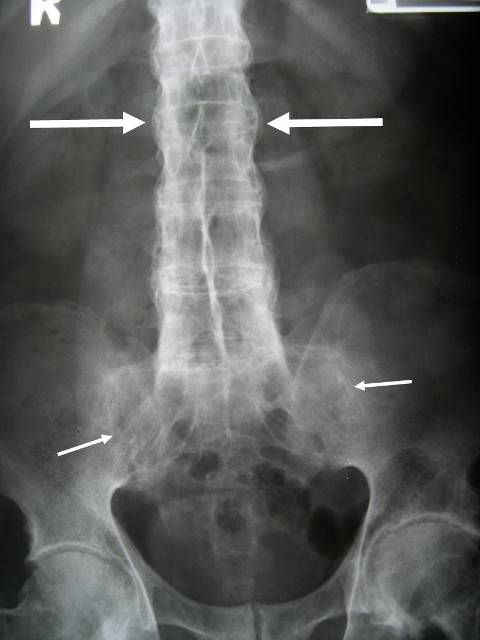

สำหรับอาการปวดหลังเรื้อรังและไม่ได้เกิดจากการได้รับอุบัติเหตุบริเวณหลังนำมาก่อน อาจทำให้คนทั่วไปเข้าใจว่าเป็นผลมากจากการนั่งทำงานหน้าคอมพิวเตอร์ การจัดท่านั่งทำงานอย่างไม่เหมาะสม หรืออาการจากออฟฟิศซินโดรม ซึ่งโรคข้อกระดูกสันหลังอักเสบชนิดติดยึดนี้ หากปล่อยเอาไว้เรื้อรังก็จะส่งผลให้กระดูกสันหลังเชื่อมติดกันถาวร เกิดภาวะหลังค่อมหรือหลังแข็ง หรือร้ายแรงจนถึงขั้นเกิดการติดกันของกระดูกสันหลังส่วนทรวงอก ทำให้หายใจเข้าได้ไม่เต็มที่ การเชื่อมติดกันของกระดูกสันหลังส่วนคอจะทำให้ไม่สามารถก้ม เงย หรือหมุนบิดคอได้ นอกจากอาการทางกระดูกสันหลังแล้ว โรคนี้ยังมีอาการแสดงที่ระบบข้อ คือ มีข้อรยางค์อักเสบ และมีอาการแสดงนอกระบบข้อ เช่น อาการตาแดงจากม่านตาอักเสบ เป็นต้น ดังนั้น การหันมาให้ความสำคัญกับอาการปวดหลังเรื้อรังจึงเป็นเรื่องสำคัญ ควรทำการปรึกษาแพทย์เพื่อให้การวินิจฉัยและรักษาที่เหมาะสมต่อไป